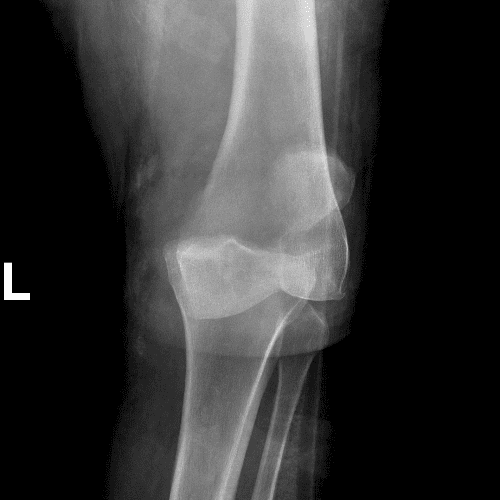

Simula o plantão incluindo casos sutis ou difíceis e alguns normais.